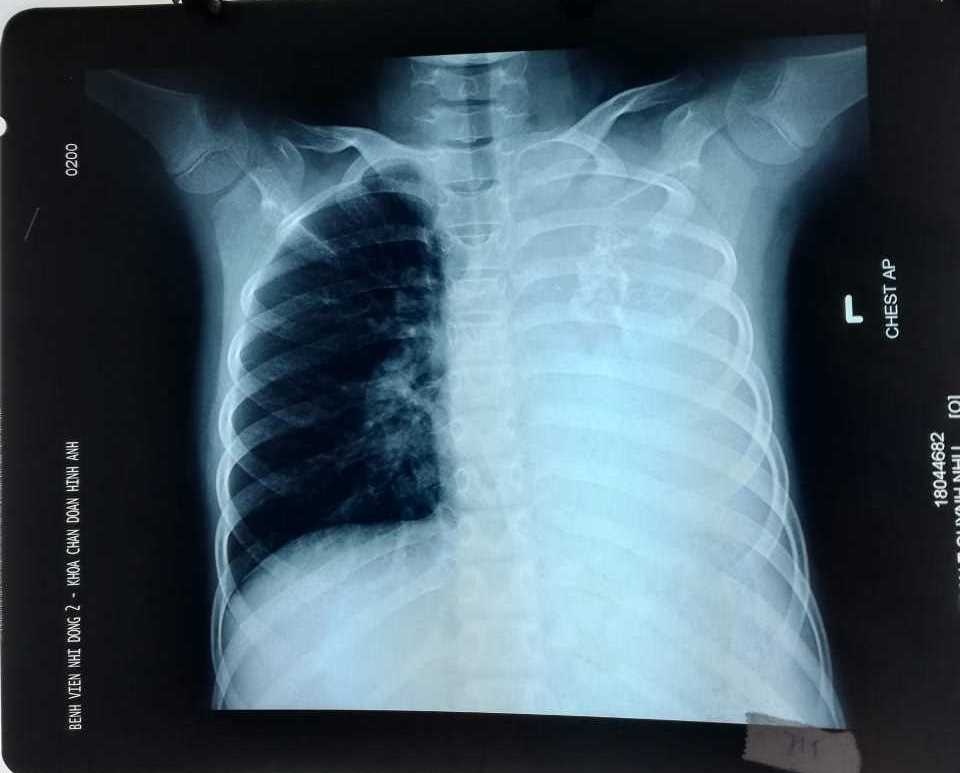

Theo thông tin từ Bệnh viện Nhi Đồng 2, TP.HCM, bệnh nhi T.T.Q.N, 10 tuổi ở Đồng Nai được người nhà đưa đi khám do tình trạng ho kéo dài, khó thở khi gắng sức. Qua hình ảnh CT scan ngực, các bác sĩ đã phát hiện một khối u phổi khổng lồ xâm lấn toàn bộ phổi trái gây tắc đồng thời phế quản gốc trái và động mạch phổi trái khiến bệnh nhi chỉ hô hấp bằng phổi bên phải.

| Khối u phổi trên phim chụp ngực. Ảnh: BSCC. |